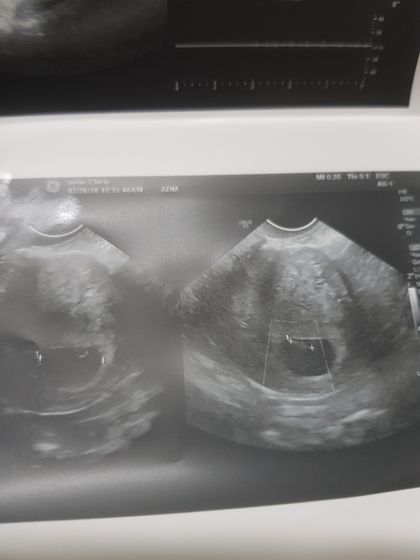

Всем привет. Сходила на узи иииии… 6.5 недель сердцебиение +, плод в матке. Все ничего но сказали есть 3 кисты в правом яйчнике. У меня никогда такого не было. Даже не представляю что это такое. Ну и все кто знает про меня у меня стоит стент в мочеточечнике который из за маленького срока не могут убрать. Сижу жду врача уролога. Будут обсуждать когда можно убрать. Кстати не поиму на фото где там эмбриончик.